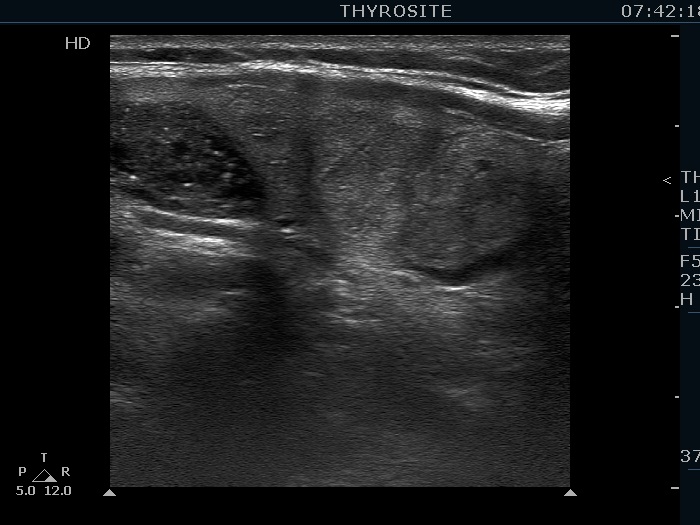

Intranodular hyperechogenic figures - case 155

Three years after the previous examination (ultrasonographic picture 7)

Left lobe, another longitudinal scan.